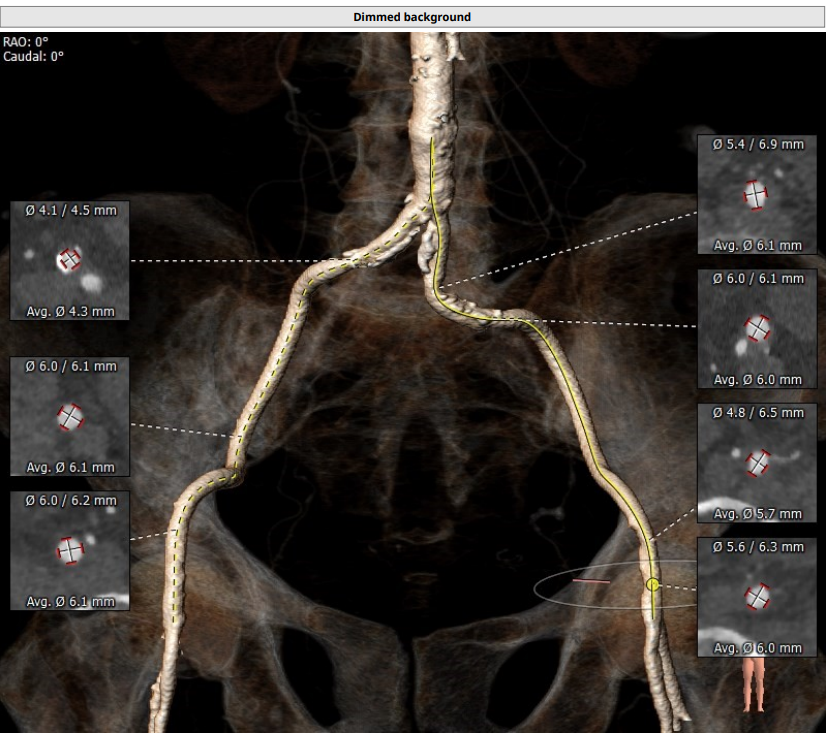

瓣环平面相关:

面积为345.8 mm²;

周长为67.2mm;

周长导出径为21.4mm;

面积导出径为21.0mm;

平均径为21.1mm;

根据瓣环径及瓣上结构,FEops优先推荐L26号,备选L23号。

术前CT评估

升主动脉直径:30.1mm,心脏夹角:40度

• 三叶式主动脉瓣,窦部空间空间小,短径仅有21.5mm。

• 钙化轻度,集中在左冠瓣叶游离缘及无冠瓣叶游离缘。